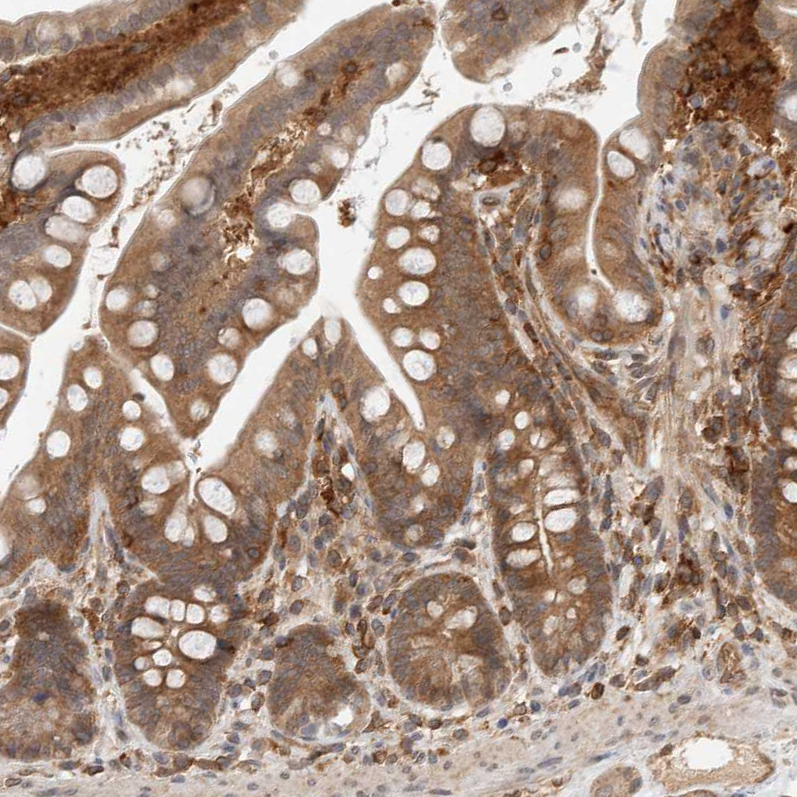

Immunohistochemistry analysis in human lymph node and cerebral cortex tissues using HPA027305 antibody. Corresponding NFKB1 RNA-seq data are presented for the same tissues.